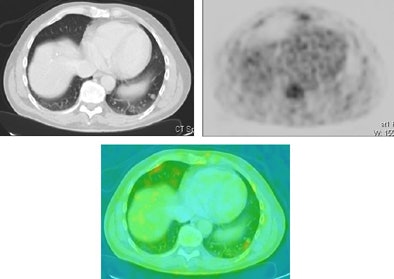

![]() |

| A 55-year-old man with colorectal carcinoma. Patient underwent a PET/CT examination for tumor staging. CT showed a nodular lesion in the left lower lobe suspect for lung metastasis. PET examination could not reveal a suspected hot spot, but when the PET-CT correlation images were evaluated, a subtle hot spot was detected at the place of the lung nodule, which confirmed the metastatic origin of this nodule. Images courtesy of Dr. Walter De Wever. |